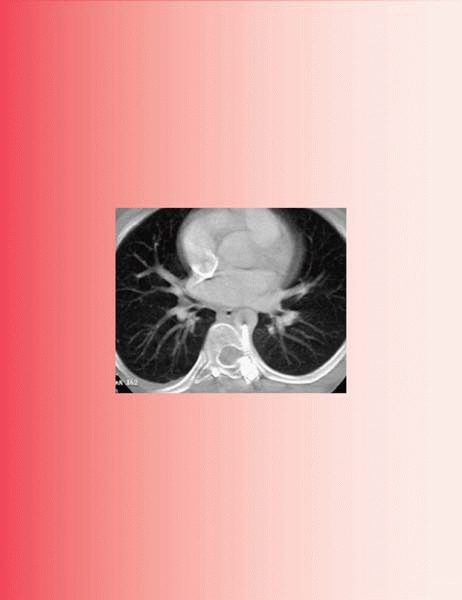

Remember first to look beyond the spine on radiographs for hidden trouble (Fig. 19-9)

▪ FIGURE 19-9

Remember to look beyond the spine on each radiograph. The need for this is aptly demonstrated here: the child’s right hip was noted to be at risk (arrow). This is easy to overlook during a scoliosis evaluation, but may be made to appear obvious to a jury years later. |